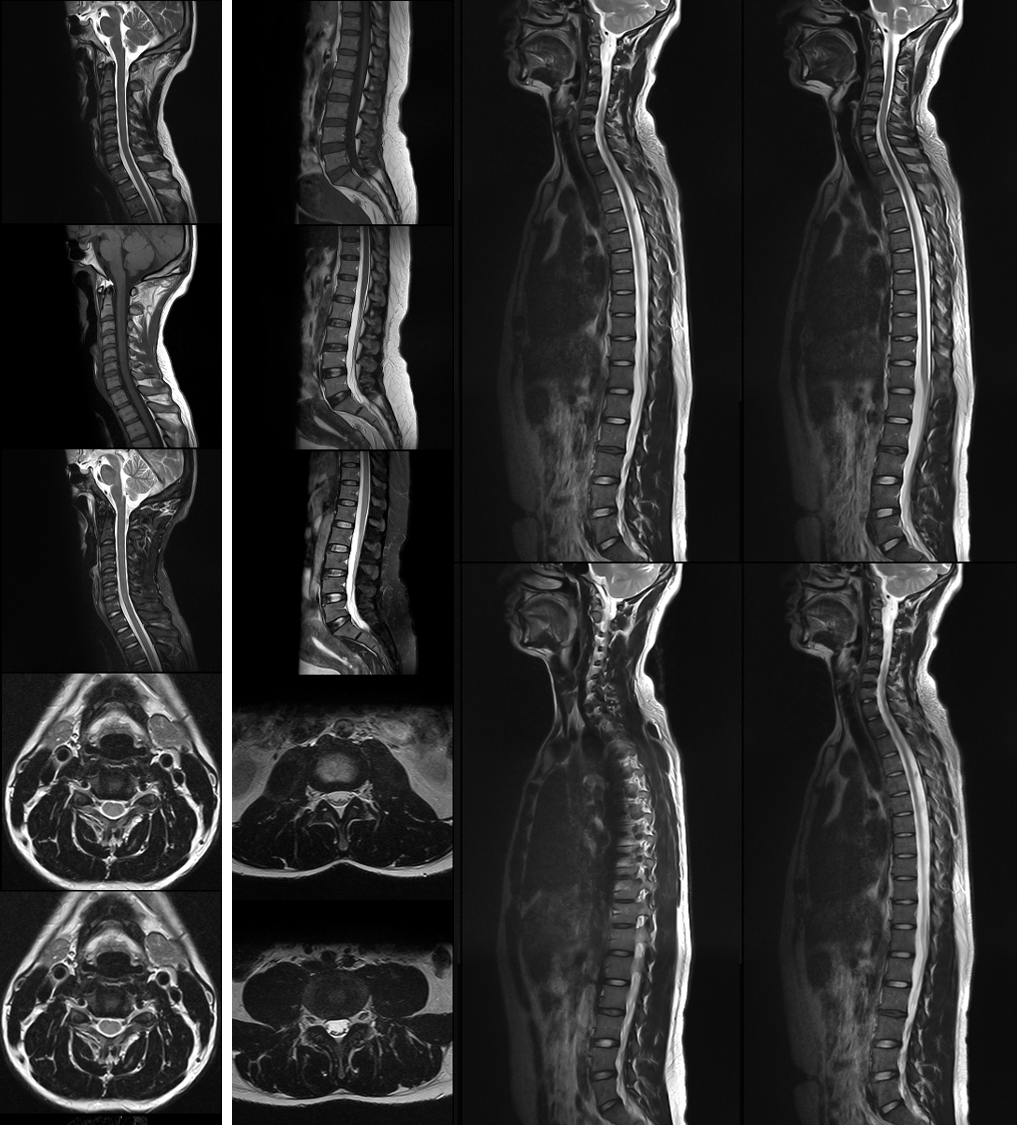

MR

¾±×µ¡¢¡¢¡¢Ñü×µ¡¢¡¢¡¢È«¼¹Öù